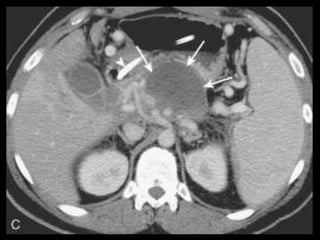

Pseudocistos

Coleções encapsuladas e uniloculadas de líquido

pancreático e material necrosado e proteináceo;

São necessárias 4 semanas ou mais para que um

pseudocisto evolua de uma coleção líquida aguda;

Mais comumente peripancreáticos, mas podem ser

observados no mediastino e na pelve;

Importância do contraste oral positivo;

Metade dos pseudocistos regride

espontaneamente;

Sintomas dependem

Pseudocistos-TC

Coleção líquida redonda ou oval, com uma parede

fina ou espessa, que apresenta intensificação pelo

contraste;

RM: lesão uniloculada bem definida, hipointensa

em T1 e hiperintensa em T2;

Bolhas de gás: infecção, fístula ou à cistostomia

interna;

Hemorragia aguda dentro do cisto: hiperdensa

Estenose ou oclusão venosa, com formação de

varizes ou pseudoaneurismas.